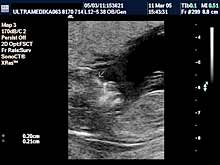

A) I trimestar do 14

nedelje gestacije

(3 meseca + 2 nedelje)

Indikacije za ultrazvučni pregled:

- Izostanak menstruacije, procena vitalnosti rane trudnoće,

procena materične i/ili postojanje vanmaterične trudnoće.

(Od 4-7 nedelje gestacije, ili prva 2 meseca od prvog dana zadnje

menstruacije).

Način pregleda:

- transabdominalno i/ili endovaginalno

(bez prethodnog punjenja

mokraćne bešike).

Primenjena tehnika:

- Broadband 2D,

- harmonik mod,

- Sono CT,

- XRes,

- 3D Sono CT,

- CPA.